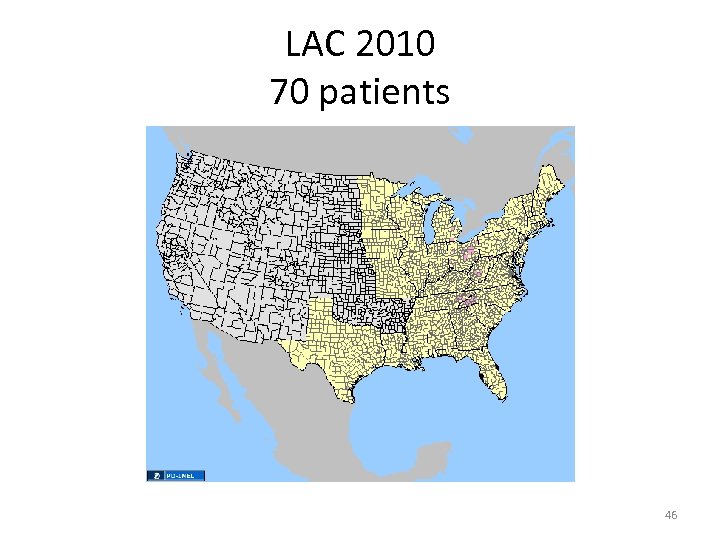

LAC 2010 70 patients 46